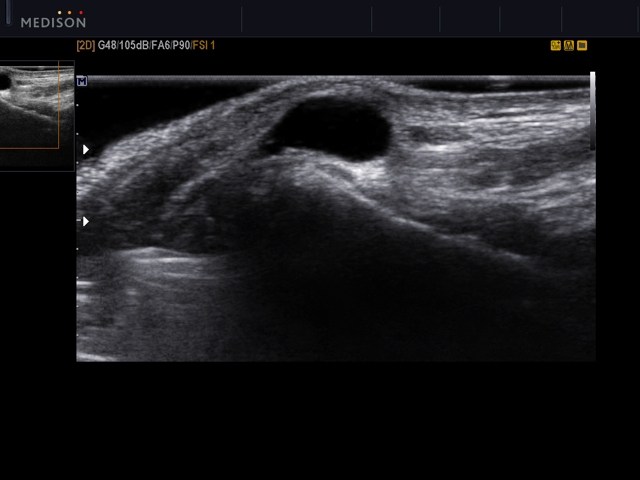

Лечение гигромы лучезапястного сустава может быть консервативным или радикальным. Выбор метода зависит от врача, который осмотрит пораженную область. Основной признак кисты — опухолевидное образование на запястье, которое может увеличиться до 2 см всего за два дня. Для диагностики применяются следующие методы:

- Ультразвуковое исследование образования и окружающих тканей;